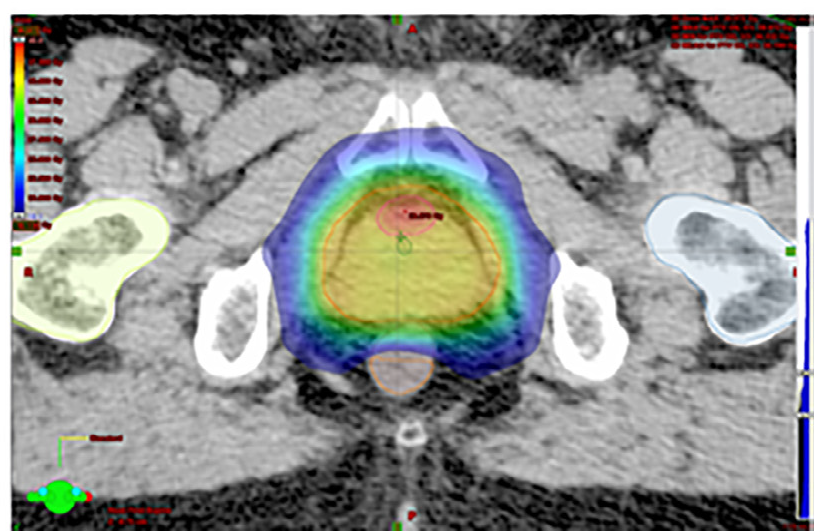

Esempio di piano di cura radioterapico per il trattamento del tumore alla prostata (Mambretti et al. – Radiother Oncol 2018)